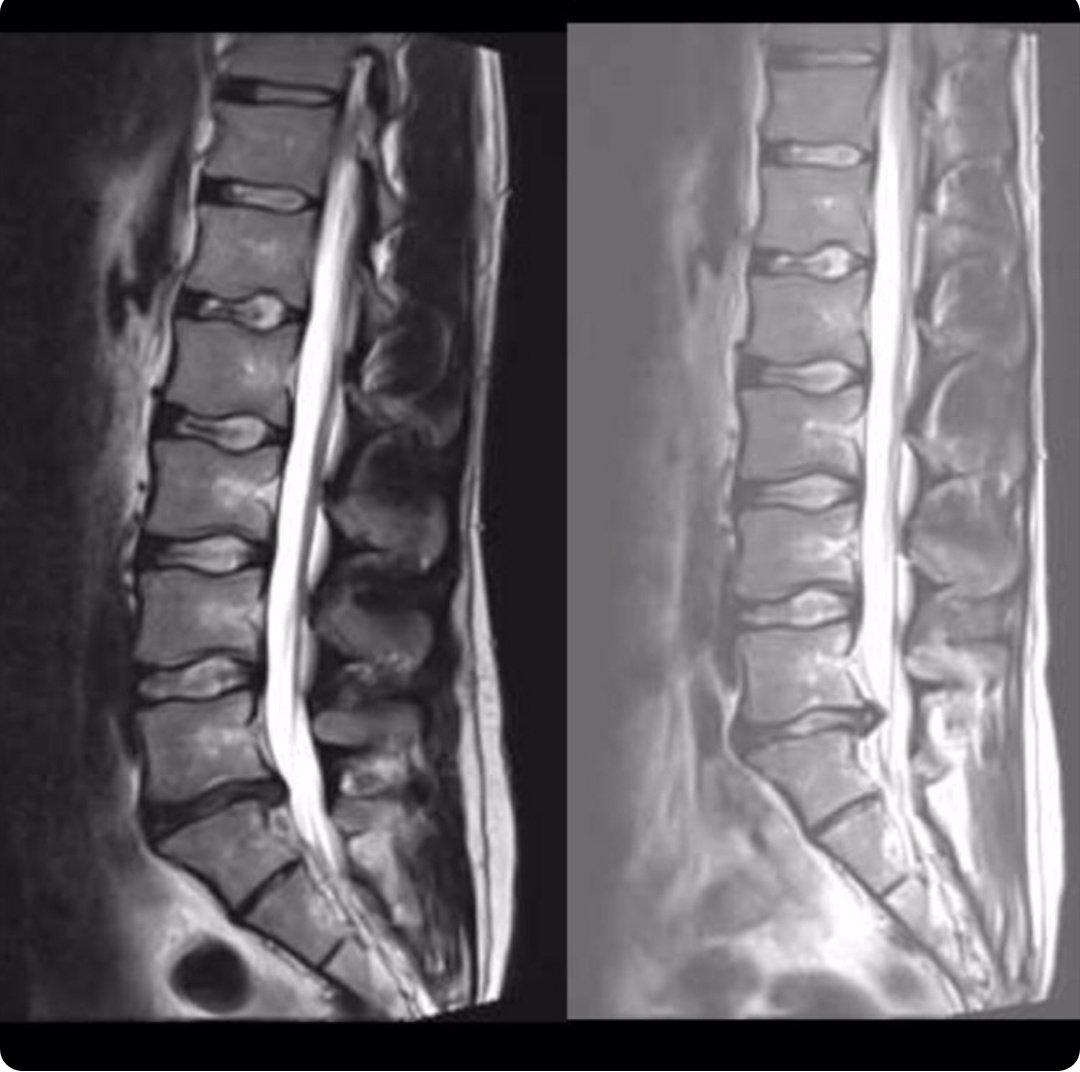

30yr old M friend w/ severe R sided LB & radicular pain for approx 9/52. Unable to stand upright, lie supine/prone, limping due to pain. Leg worse than back. Insidious onset. Trying best to stay active but struggling. Only meds that help - difene & solpadol. Has seen X2

Physiotherapists. Basic mobility/ROM work for lumbar spine which he does & no change. Has been referred to neurosurgery as intensity of pain & function have not improved. Here is his scan. Left 2017, right this week.

What advice would you give this man who is otherwise very fit and healthy and eager to return to sport?